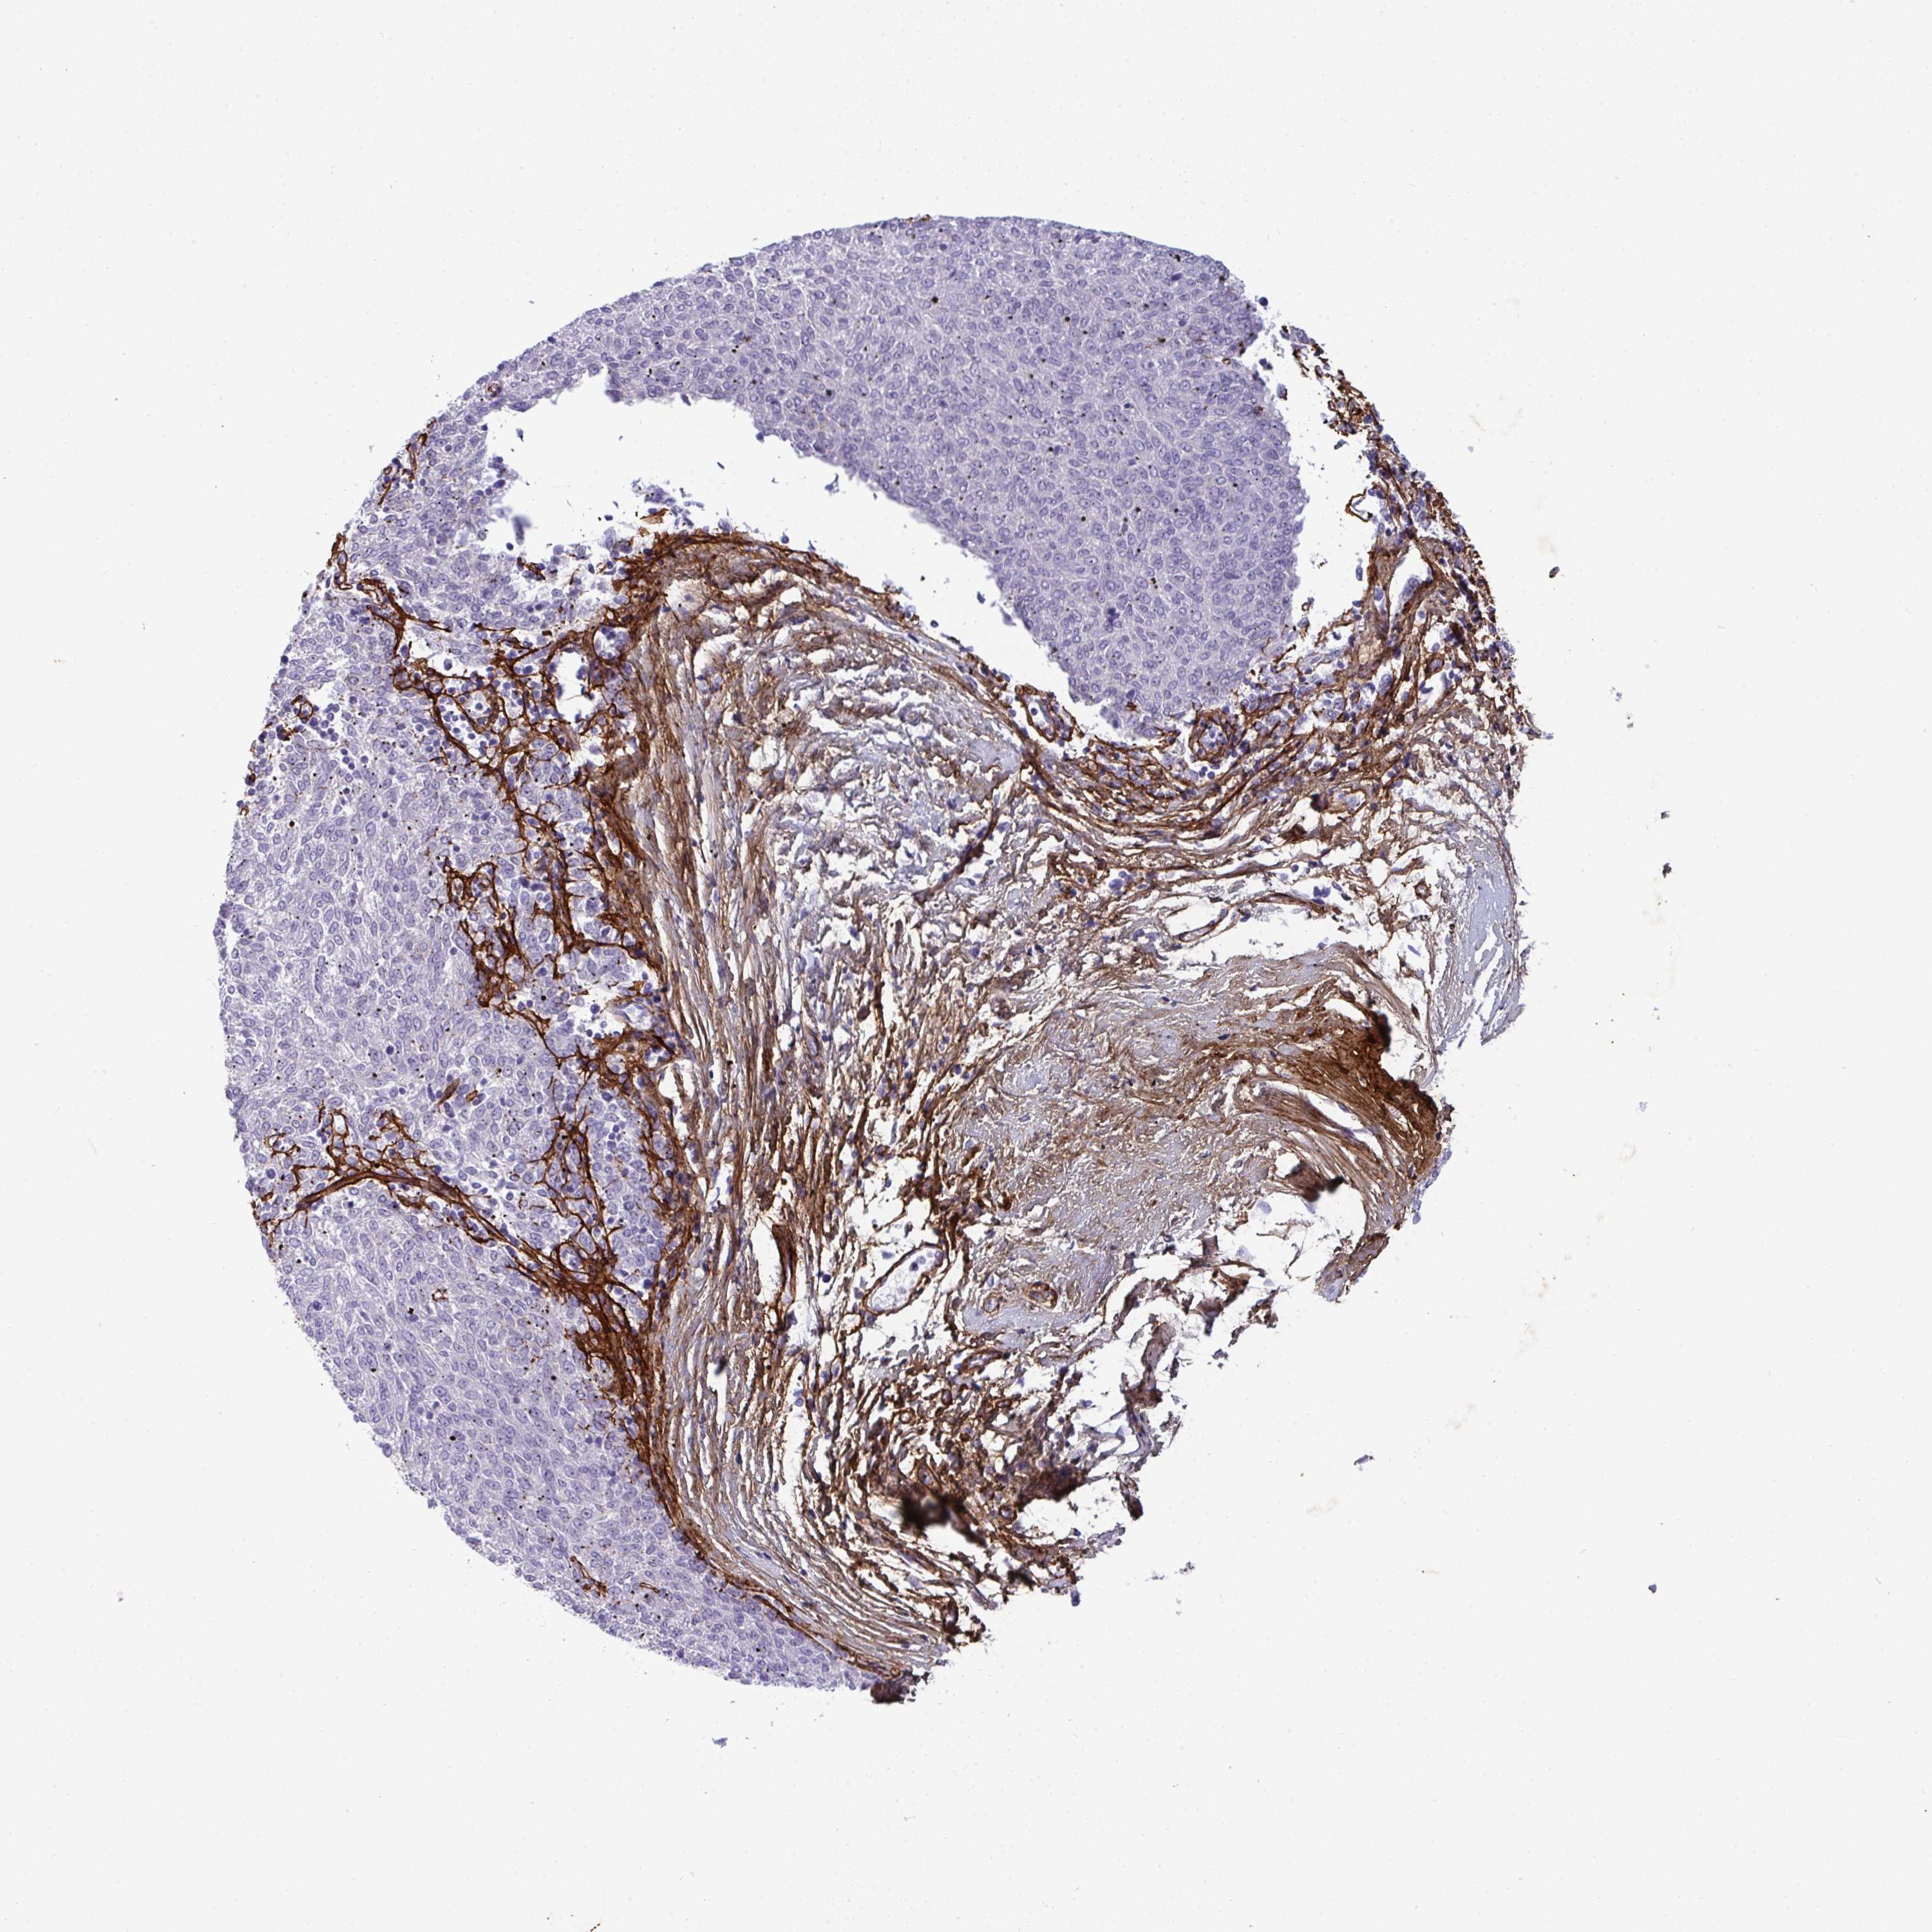

MELANOMA - Protein expressioni

A mouse-over function shows sample information and annotation data. Click on an image to view it in a full screen mode. Samples can be filtered based on level of antibody staining by selecting one or several of the following categories: high, medium, low and not detected. The assay and annotation is described here.

Note that samples used for immunohistochemistry by the Human Protein Atlas do not correspond to samples in the TCGA dataset.

Antibody stainingi

Antibody staining in the annotated cell types in the current human tissue is reported as not detected, low, medium, or high, based on conventional immunohistochemistry profiling in selected tissues. This score is based on the combination of the staining intensity and fraction of stained cells.

Each image is clickable and will lead to virtual microscopy that enables deeper exploration of all samples and also displays staining intensity scores, fraction scores and subcellular localization as well as patient and tissue information for each sample.

Antibody HPA058975

Malignant melanoma, Metastatic site

Malignant melanoma, NOS